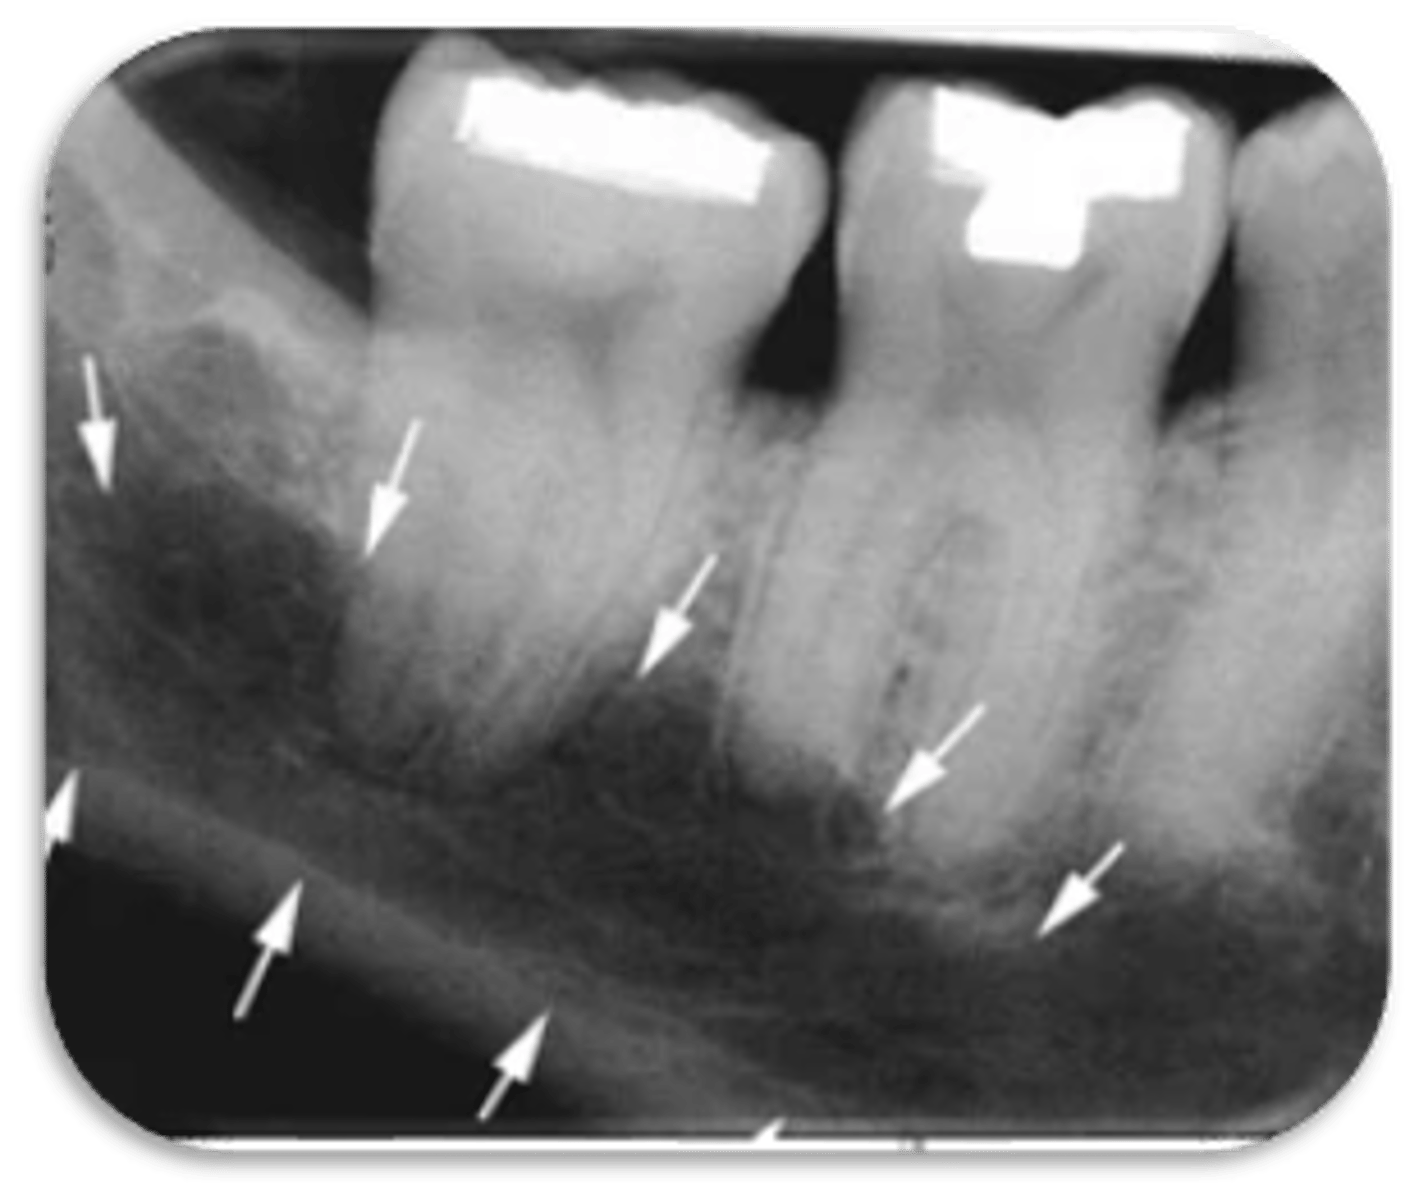

ID the structure with the purple arrow:

external oblique line

ID the structure with the green arrow:

inferior alveolar nerve canal

ID the structure:

submandibular gland fossa